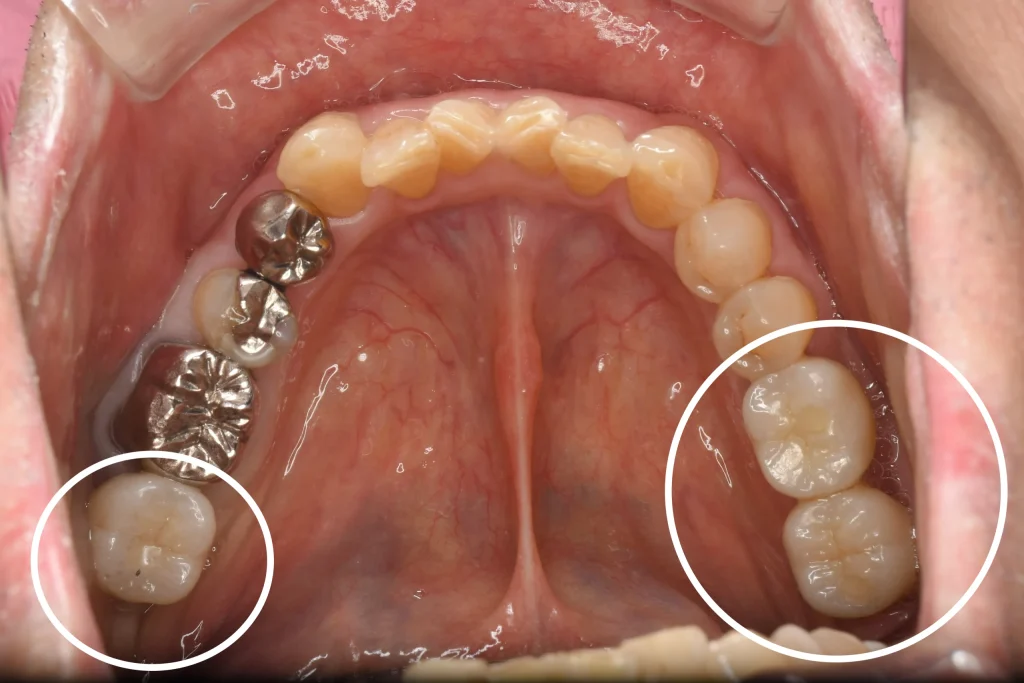

10年以上当院に定期検診で通われている患者様です。

この度、何度も再治療を行い残すことが不可能になってしまった奥歯をやむなく抜歯し、その失った奥歯に対し、入れ歯以外の方法で回復したいとのことでインプラントのご相談を受けました。

骨の幅にあまり余裕がありませんでしたので、小規模の骨造成をとインプラントを行いました。

以前行った左側のインプラントと含めると計3本のインプラントが埋入されておりますが、トラブルなく現在も食事が取れているとのことです。